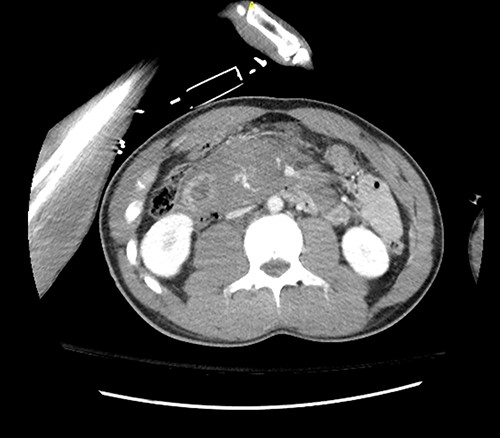

Here, we report a case of a 21-year-old man who was admitted to our hospital following a motor vehicle collision where he was a pedestrian, hit by a car and pushed against the bumper of another car. Upon arrival to the hospital, he was conscious and oriented, with normal vital signs. Abdominal examination revealed ecchymosis over the epigastric area with tenderness, however, no distention was noticed. Focused assessment with sonography for trauma result was positive in the right upper quadrant. His initial blood test results revealed a white blood cell (WBC) count of 26.5 × 109 cells/l and a hemoglobin level of 150 g/l. His serum amylase and lactic acid levels were 92 U/l and 4.53 mmol/l, respectively. His base deficit was 4.3. He underwent abdominal computed tomography (CT) with oral contrast, which showed query duodenal and possible pancreatic transection with active arterial extravasation (Figs 1–3). In addition, CT revealed a comminuted right intertrochanteric femoral fracture without associated vascular injury.

Despite its limitations in distinguishing between duodenal hematoma and duodenal perforation, CT with intravenous and intraluminal contrast remains the gold standard diagnostic test in stable patients with blunt abdominal trauma [1]. In the reported case, CT revealed duodenal and possible pancreatic transection with active arterial extravasation.